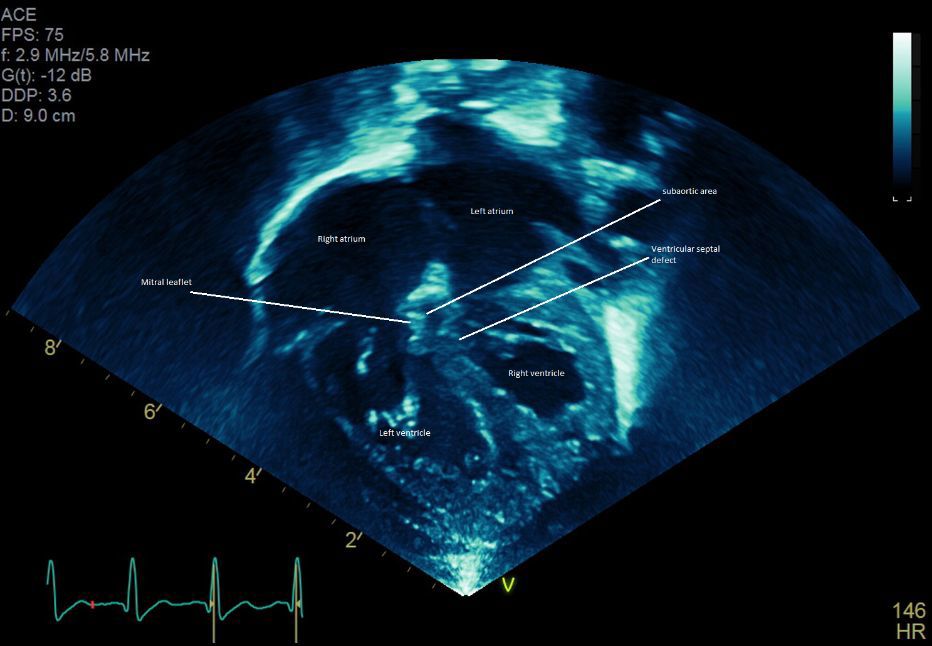

One such patient was an infant diagnosed in utero via fetal ultrasound with an unusual form of transposition of the great arteries. Deoxygenated blue blood entered the right atrium which connected to the left ventricle and then the aorta, and oxygenated red blood entered the left atrium which connected to the right ventricle and then the pulmonary artery. The patient also had a very large ventricular septal defect (VSD) connecting both ventricles and severe narrowing between the left ventricle and the aorta. It was apparent early on that the patient was becoming fairly blue as deoxygenated blood was being directed towards the aorta. A balloon atrial septostomy performed in the first few days of life resulted in some improvement. However, significant tachycardia persisted. It became clear that the degree of subaortic narrowing was more severe than originally anticipated, and this resulted in significantly depressed left ventricular function. Something needed to be done soon.

The cardiothoracic surgical team led by Charles Huddleston, M.D., and members of the cardiac medical team including Wilson King, M.D., agreed that surgery was required. Due to the rarity of this condition, there was controversy over how to repair the infant’s heart. A neonatal atrial switch seemed to be the best strategy. This is a challenging operation that redirects the oxygenated blood to the aorta and deoxygenated blood to the pulmonary arteries by creating intraatrial baffles. Addressing the subaortic stenosis was extremely problematic, as it appeared that much of the obstruction was caused by tissue that was extremely close to the mitral valve. Damaging the mitral valve would result in significant problems for the patient. “After reviewing the echocardiogram, many of our cardiologists as well as the referring cardiologists were convinced it was part of the  structural integrity of the mitral valve and resecting it would mean replacement of that valve and subjecting the child to lifelong disease. Others thought it was accessory tissue not critical to mitral valve function. From the imaging studies alone, it was impossible to tell, limiting our ability to confidently develop a surgical plan,” said Dr. Huddleston (figures 1,2,3,4). For complex cases like this, the Cardinal Glennon surgical team relies on 3D printing.

3D model of the heart of a 5-day-old infant with congenitally corrected transposition of the great arteries with a large ventricular

septal defect and severe subaortic stenosis. (AO – aorta, ASD – atrial septal defect, RA – right atrium, LV – left ventricle, MV – mitral valve,

VSD – ventricular septal defect)